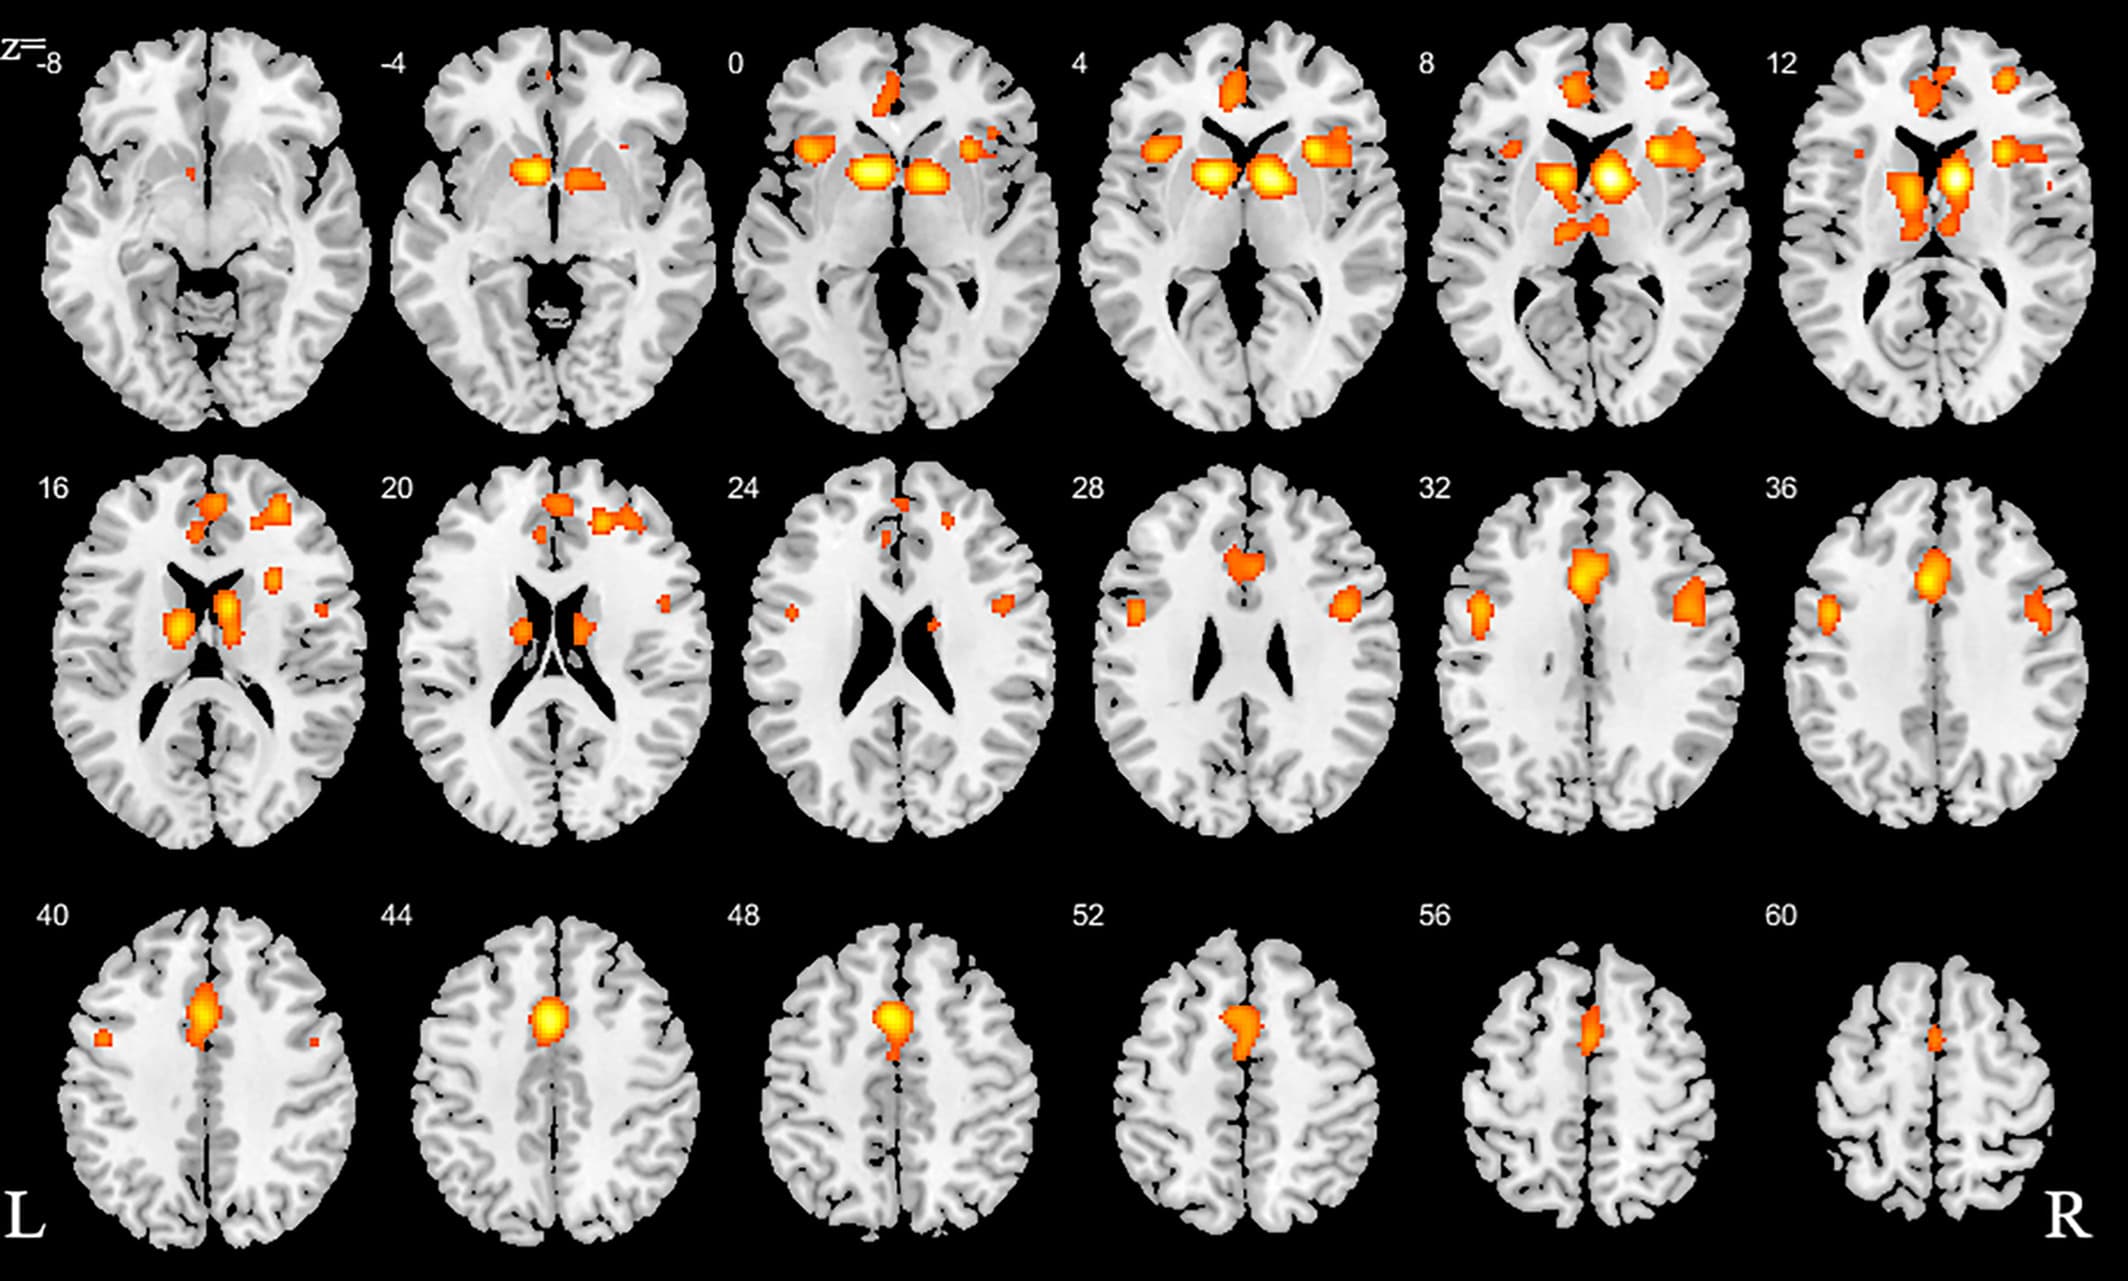

We initially conducted a main meta-analysis that incorporated the ALE maps from all SUDs versus the respective control groups (Step 1). This analysis aimed at determining neurofunctional alterations across all SUDs and revealed neurofunctional alterations primarily located in the dorsal striatum, including the caudate and putamen as well as the prefrontal, limbic and insular cortex, including inferior, superior, and medial frontal regions as well as the anterior cingulate cortex (ACC) and the anterior insula (Figure 2, Table 2).

Figure 2. ALE for combined studies. All slices in transverse view with ascending slice number. Displayed at FWE < 0.05

Table 2. Detailed peak coordinates for the combined studies with the number of clusters for each volume